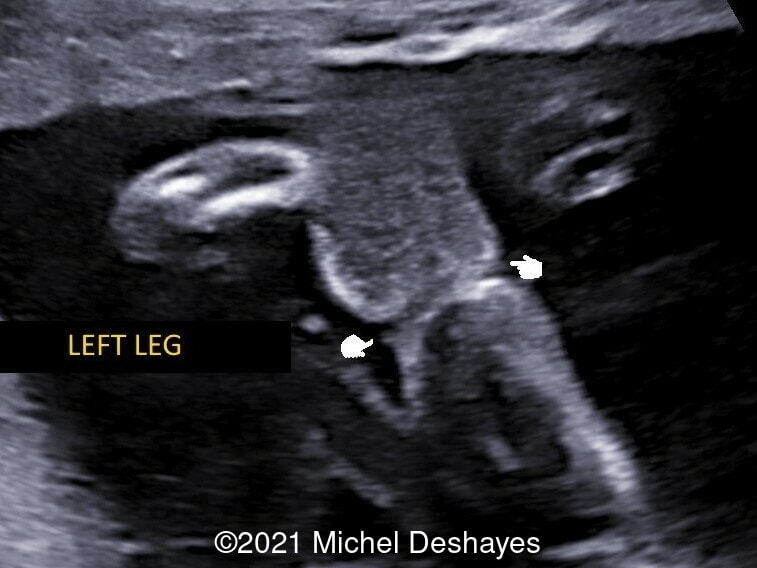

• Images 2-4: Ultrasound at 22 weeks gestation showing left foot edema with narrowing and stricture of the soft tissue due to an amniotic band (marked as ? on image 2).

We considered fetal surgery to release the amniotic bands and alleviate the strictured tissues, however at 24 weeks gestation there was fetal demise. External examination of the fetus confirmed the left foot edema and stricture of the left leg soft tissue. Additionally, there was amputation of several fingers of the right hand that was missed on prenatal ultrasound (Image 4).